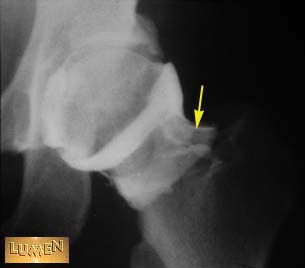

Question: Identify.

Hip joint capsule.